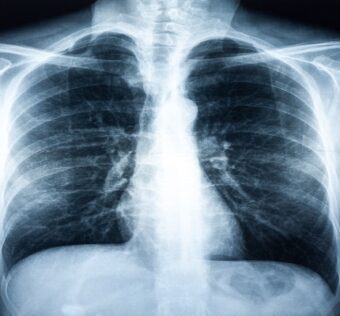

![]() InHealth partners with Qure.ai for AI-powered chest x-ray solution

Digital Health - (Friday June 2, 2023) InHealth is set to deploy Qure.ai’s artificial intelligence solution to help with the classification of chest x-rays into normal and abnormal exams, enhancing the quality and accuracy of reporting to improve patient outcomes.The AI… ![]() HCP Marketing in the Pharma Industry: A Comprehensive Strategy for Engaging Healthcare Professionals